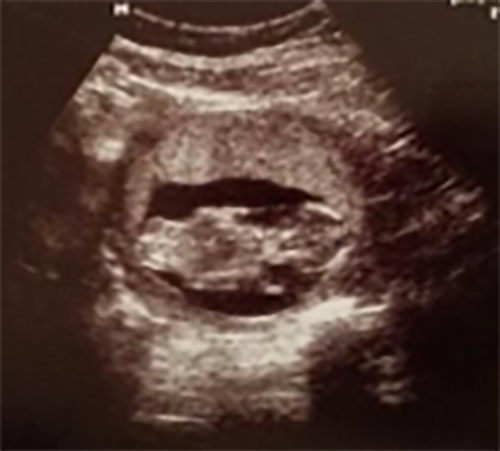

Trong các phòng thí nghiệm IVF, nơi trứng, tinh trùng và phôi cực kỳ nhạy cảm, chất lượng không khí quyết định trực tiếp đến tỷ lệ thụ tinh và làm tổ.

Phôi thai đặc biệt dễ tổn thương trước các hạt bụi siêu mịn và khí độc.